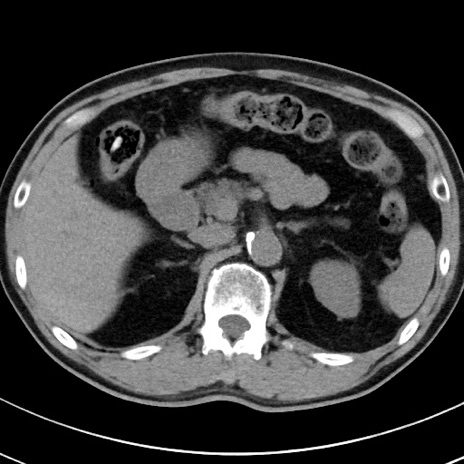

【腹部TIPS】症例29 参考症例 CT(横断像)

症例

70歳代男性